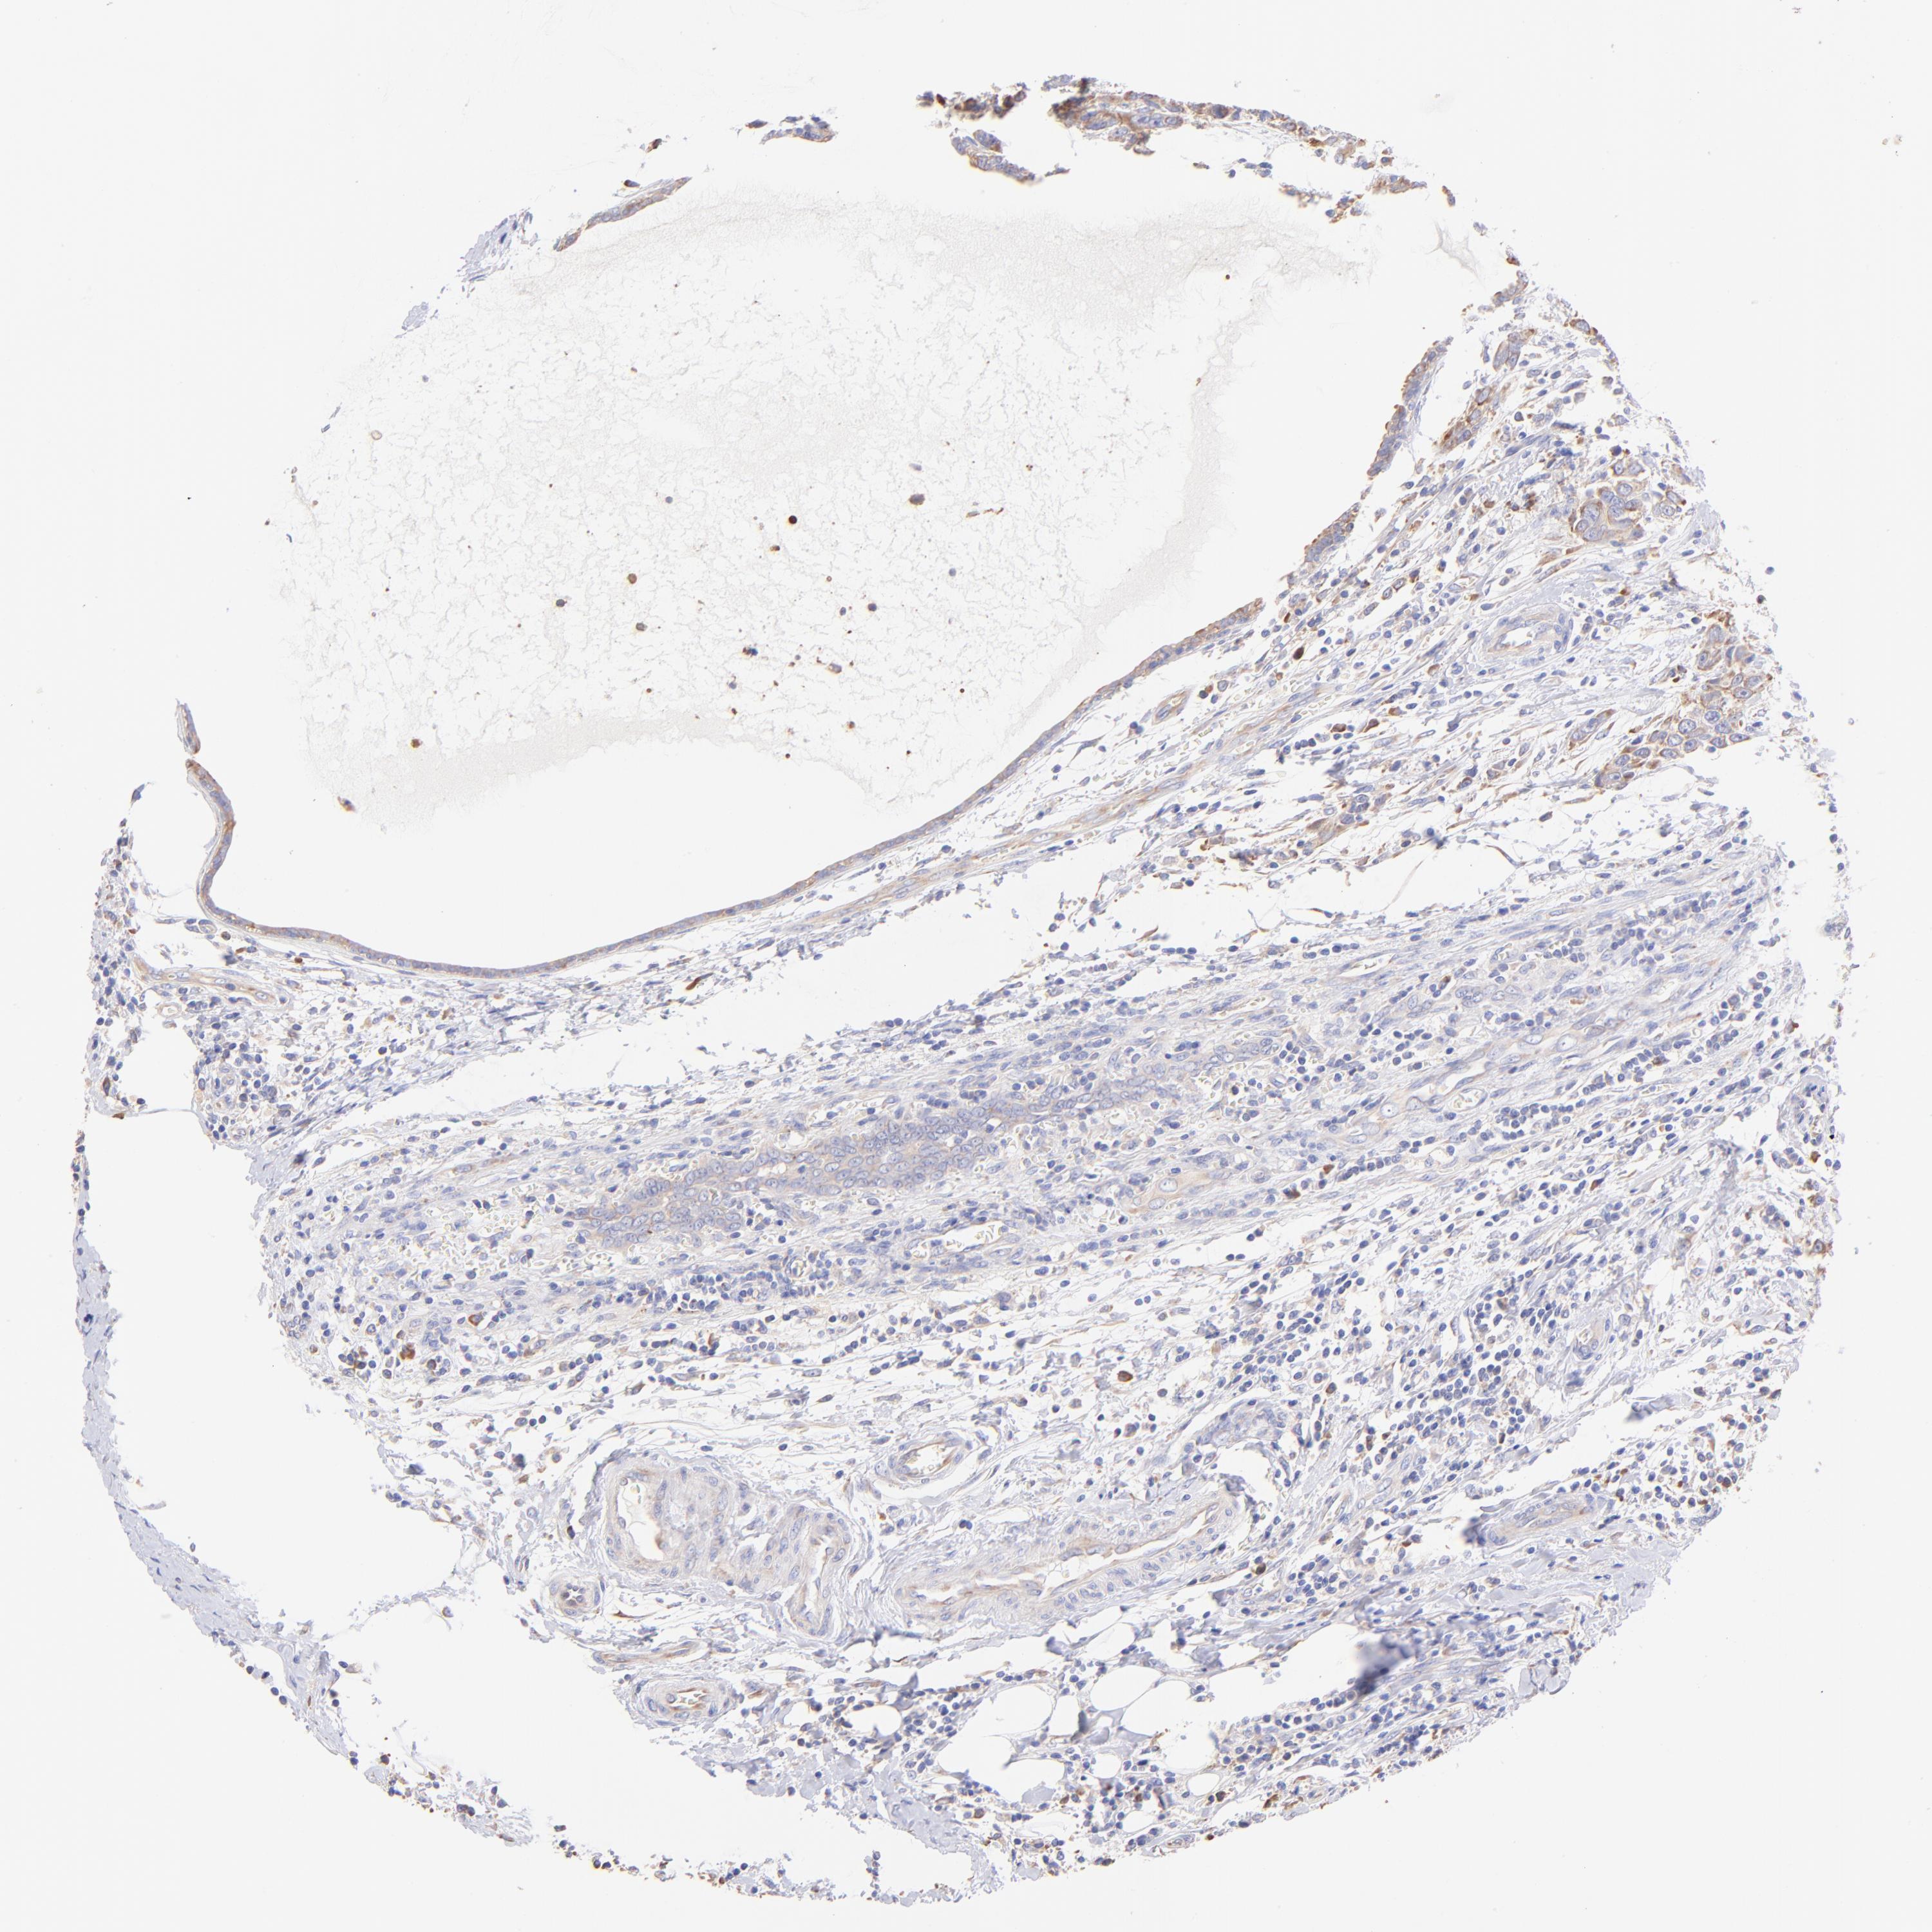

BRCA TCGA BRCA VALIDATION PROTEIN EXPRESSION

ANTIBODIES

AND

VALIDATION